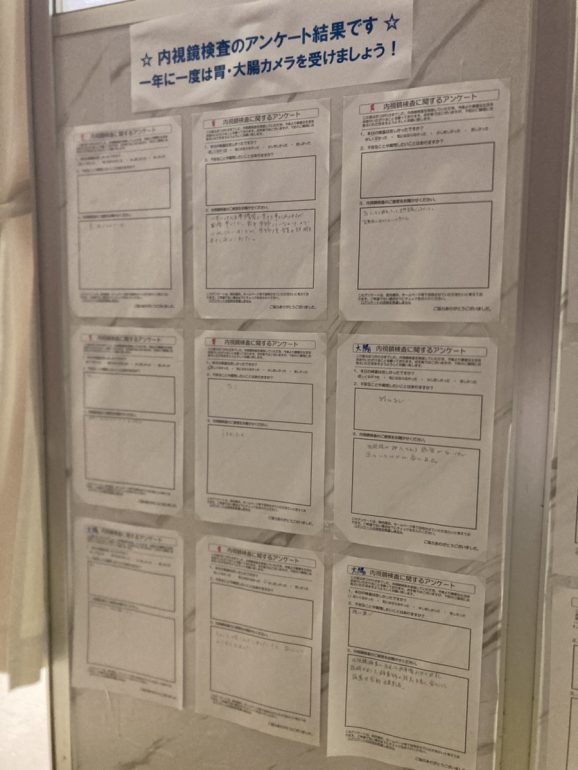

2021年9月から当院で内視鏡検査を受けられた方へのアンケートを開始しました。

80%の患者さまが、「苦しくなかった」「気にならなかった」とお答えいただけました!

苦しくなかった 33名 68%

気にならなかった 6名 12%

少し苦しかった 9名 18%

苦しかった 0名 0%

麻酔を使わずに検査を受けられた方々に「少し苦しかった」とのご回答が多かったようです。今後も苦痛の少ない内視鏡検査を目指して精進いたします。

【アンケートに実際に書き込んで頂いたご意見ご感想(原文のまま、一部抜粋)】

当院では内視鏡検査の品質向上のため、患者様にアンケートのご協力をお願いしております。

貴重なご意見ありがとうございます。

今後も安心・安全な医療を皆様に提供できるようスタッフ一同努めて参ります。